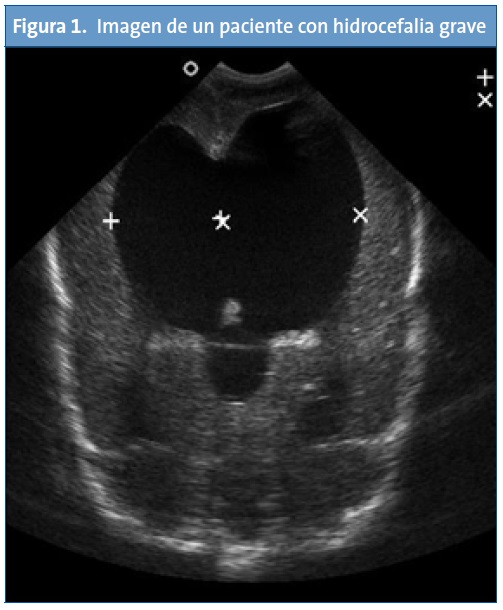

La realidad asistencial pediátrica actual, digamos “no oficial”, es otra bien distinta, pues la técnica ya está siendo utilizada a diario por pediatras españoles. El ejemplo más claro es la subespecialidad de Cardiología Pediátrica, en la que resulta imprescindible. En los servicios pediátricos, las diferentes subespecialidades hacen uso de la ecografía: los neuropediatras o neonatólogos realizan ecografías cerebrales transfontanelares en neonatos y lactantes (Fig. 1). Los intensivistas pediátricos y neonatales acceden a vías centrales guiados por ecografía7-8, o para documentar un neumotórax9 o asegurar la intubación traqueal para distinguirla de la esofágica10. Los gastroenterólogos pediátricos realizan ecografías abdominales donde valoran el hígado, el bazo o cuantifican el reflujo gastroesofágico, e incluso realizan seguimiento en postrasplantados hepáticos para observar signos de rechazo. No son pocos los neonatólogos que realizan ecocardiografías “furtivas” en las guardias ante pacientes inestables para el diagnóstico de válvulas de uretra posterior (Fig. 2) o para descartar una cardiopatía cuando no tienen un cardiólogo pediátrico a su disposición. Los médicos de Urgencias Pediátricas se forman cada vez más mediante cursos llamados Eco-FAST11, que permiten diagnósticos en Urgencias ante pacientes politraumatizados para detectar líquido libre en el abdomen, ascitis, neumotórax o una pericarditis. Todos estos son unos pocos ejemplos de lo que hoy en día realizan los pediatras, a diario, con un beneficio importante de los pacientes, ya que en muchos casos es necesario obtener información inmediata y existen limitaciones como que el radiólogo no está presente o disponible, o que la técnica se realiza en un momento diferido, en el que ya no nos proporciona información o incluso que el radiólogo no tenga experiencia en población pediátrica por poner algunos ejemplos. Se han publicado recientemente resultados de trabajos de ecografía realizada por pediatras de Atención Primaria12, lo que muestra que, si bien no es una realidad todavía extendida, la ecografía para los clínicos comienza su andadura en España.

Todas las imágenes han sido realizadas por pediatras durante una guardia.